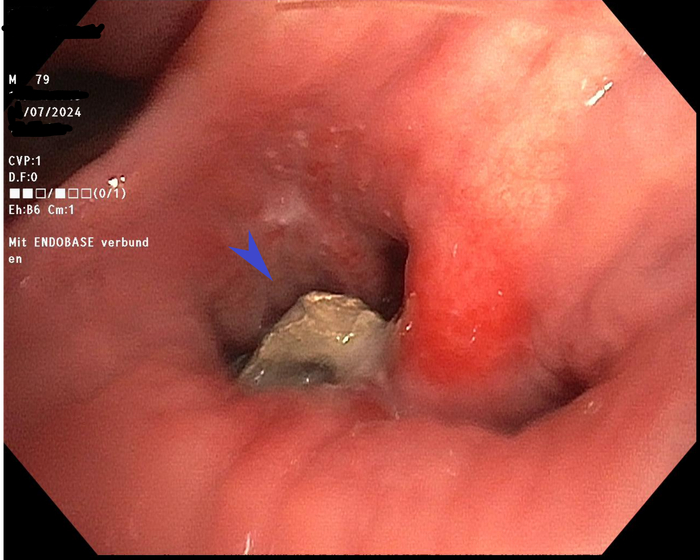

С таким предположительным диагнозом больной был направлен на бронхоскопию, в процессе выяснилось, что инородным телом являлась случайно выпавшая пломба из амальгамы: